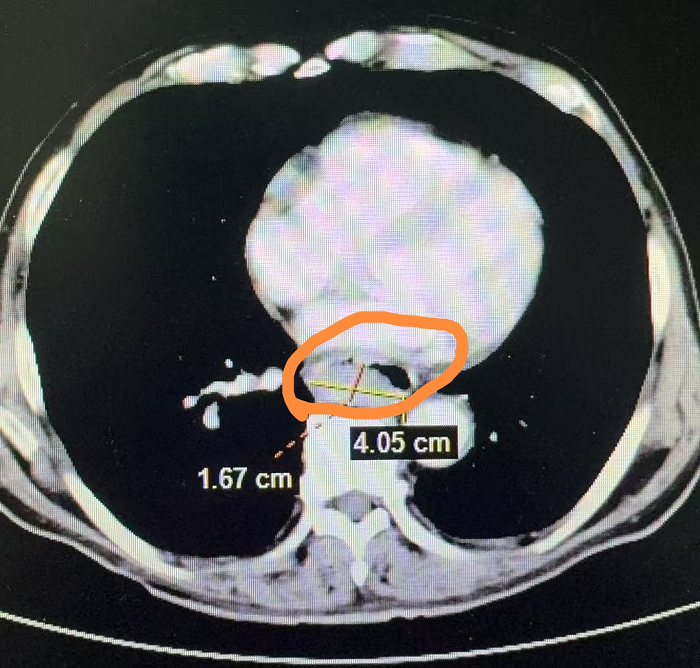

转入心胸外科后,王大爷的病情急转直下。一次进食后,他突发剧烈咳嗽,血氧饱和度持续下降,心率增快,还伴有胸闷、气促等症状。医生判断为“误吸导致的严重肺部感染和呼吸衰竭”。情况危急,麻醉科、呼吸内科和ICU迅速协同抢救,紧急为王大爷进行气管插管并转入ICU。经过积极抗感染和呼吸道管理,王大爷的肺部感染得到控制,拔管后转回心胸外科。然而,此时的他全身状态极差,无法进食,只能依靠胃管维持营养,还持续出现黑便,病情十分危重。一个严峻的两难选择摆在团队面前。若不进行手术,肿瘤将持续出血、增大,可能导致失血性休克、全身转移,危及生命;若行手术,患者全身状况极差,手术风险极高。

经过充分的术前准备,由我院心胸外科学科带头人、原上海长海医院心胸外科邹良建教授、科主任谢骏带领团队,为王大爷实施了食管癌根治术。历时三个多小时,手术顺利结束。术后,王大爷在ICU团队的精心治疗下,成功脱离呼吸机,带着气管套管转回心胸外科普通病房。接下来,王大爷还要闯过肺部感染、呼衰、吻合口或残胃瘘、血栓形成等多重难关。最终,在全体医护人员的共同努力下,术后第9天,他开始逐步拔除各类引流管;第14天,开始经口进食,从流质逐步过渡到软食;术后第21天,成功拔除气管套管,气管切开处愈合良好。